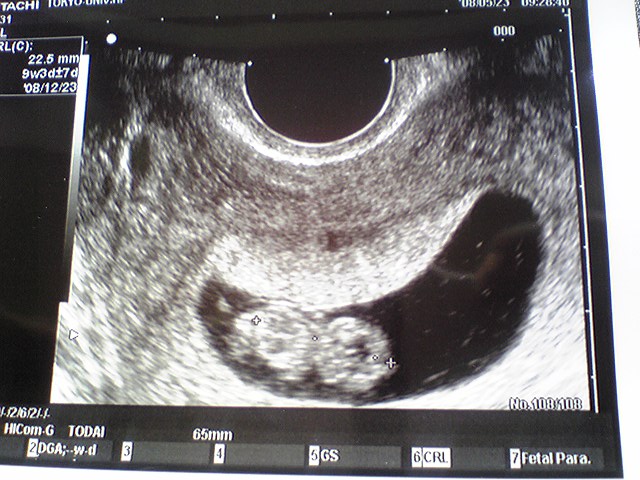

今日は検診日でした♪

まが玉からキューピーになってました!

先生の話だと、ちょぴっと出てきたお手手とあんよをピョコピョコ動かしてた!・・・らしい。

2度目の検診日。

前回「次、心拍確認できなかったら、また流産だね」って言われてたので、エコー見るのが正直怖かったんだけど・・・。

すっごーく、早くて、力強い心音が聞こえてきました。

今まで、最長10週での流産処置を受けたことがあるんだけど、それでも心音を聞いたのは初めて。

こんなに、力強いんだね!

こんなに感動したことないってくらい、感動しました

「すごく順調ですよ。良かったね。おめでとう」

初めて、聞いたおめでとうの言葉。

恥ずかしくなっちゃうくらい、長くエコーでうつしてくれて、涙があふれて、止まらない。

CRL≒1cm

力強い心音で、ワタシをホッとさせてくれた、親孝行な子です。

このままどうか、無事に、すくすく育ってね。

12月にあなたに会えるのを、楽しみにしています。